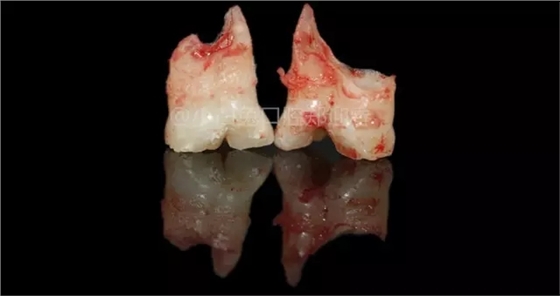

患兒,10歲,因上前牙未替換來(lái)診,查體:輕度反合,51和52、61和62均融合,且存在間隙約4mm,全面曲面斷層片顯示:11、21未萌,52、51、61、62牙根均有不同程度的生理性吸收。

拔出后的離體牙